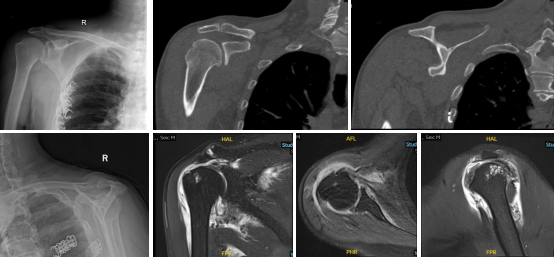

临沂市人民医院成功开展肩关节镜下改良Rosales上关节囊“W五点固定”重建术

近日,临沂市人民医院运动医学与保膝外科高万里主任及其运动医学团队,在骨科医学中心吴立生主任指导下,为一例巨大不可修复性肩袖损伤患成功实施了“肩关节镜下改良Rosales上关节囊重建术”。